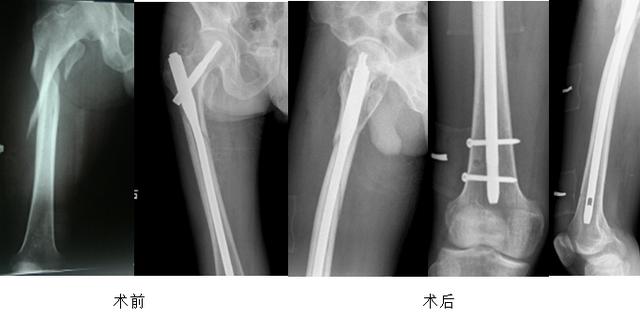

难复性股骨转子间骨折术前

术后

我们复位的技巧是在髋关节前方增加一个五公分左右的DAA切口,用以辅助复位和方便穿过钢丝,复位前尽量外旋股骨远端以帮助解锁,可以用宽骨剥插入骨折断端将骨折近端翘起,此时牵引并内旋、内收股骨远端,残余移位可以通过一条钢丝,利用过钢丝器将钢丝从髂腰肌与股骨矩之间绕过股骨捆扎复位。